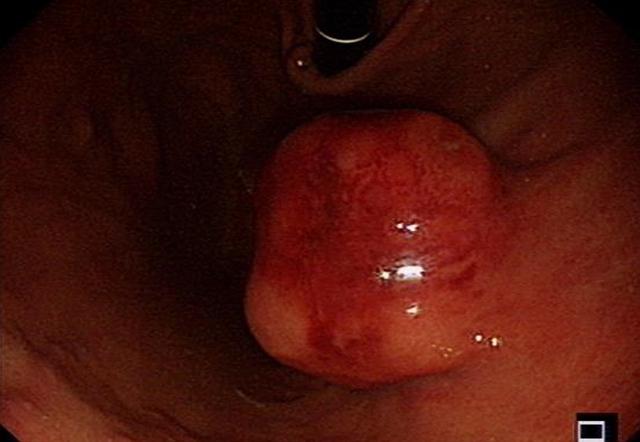

目前,李婆婆饮食恢复正常,无腹痛、腹胀等症状,“与一开始见到的她简直像两个人,在近日的胃镜复查中,她的胃壁已完成愈合,并没有肿瘤的复发”汤小伟副教授说。

术后4月后,患者复查胃镜提示胃内创面已经完全痊愈,肿瘤没有复发。